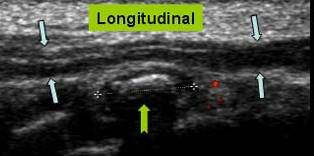

LUXATIA NERVULUI ULNAR

Nervul ulnar →

Sectiune transversala la nivelul santului epitrohleo olecranian

Nervul ulnar normal, cot in extensie →

Luxatie anterioara a nervului ulnar in flexia cotului →